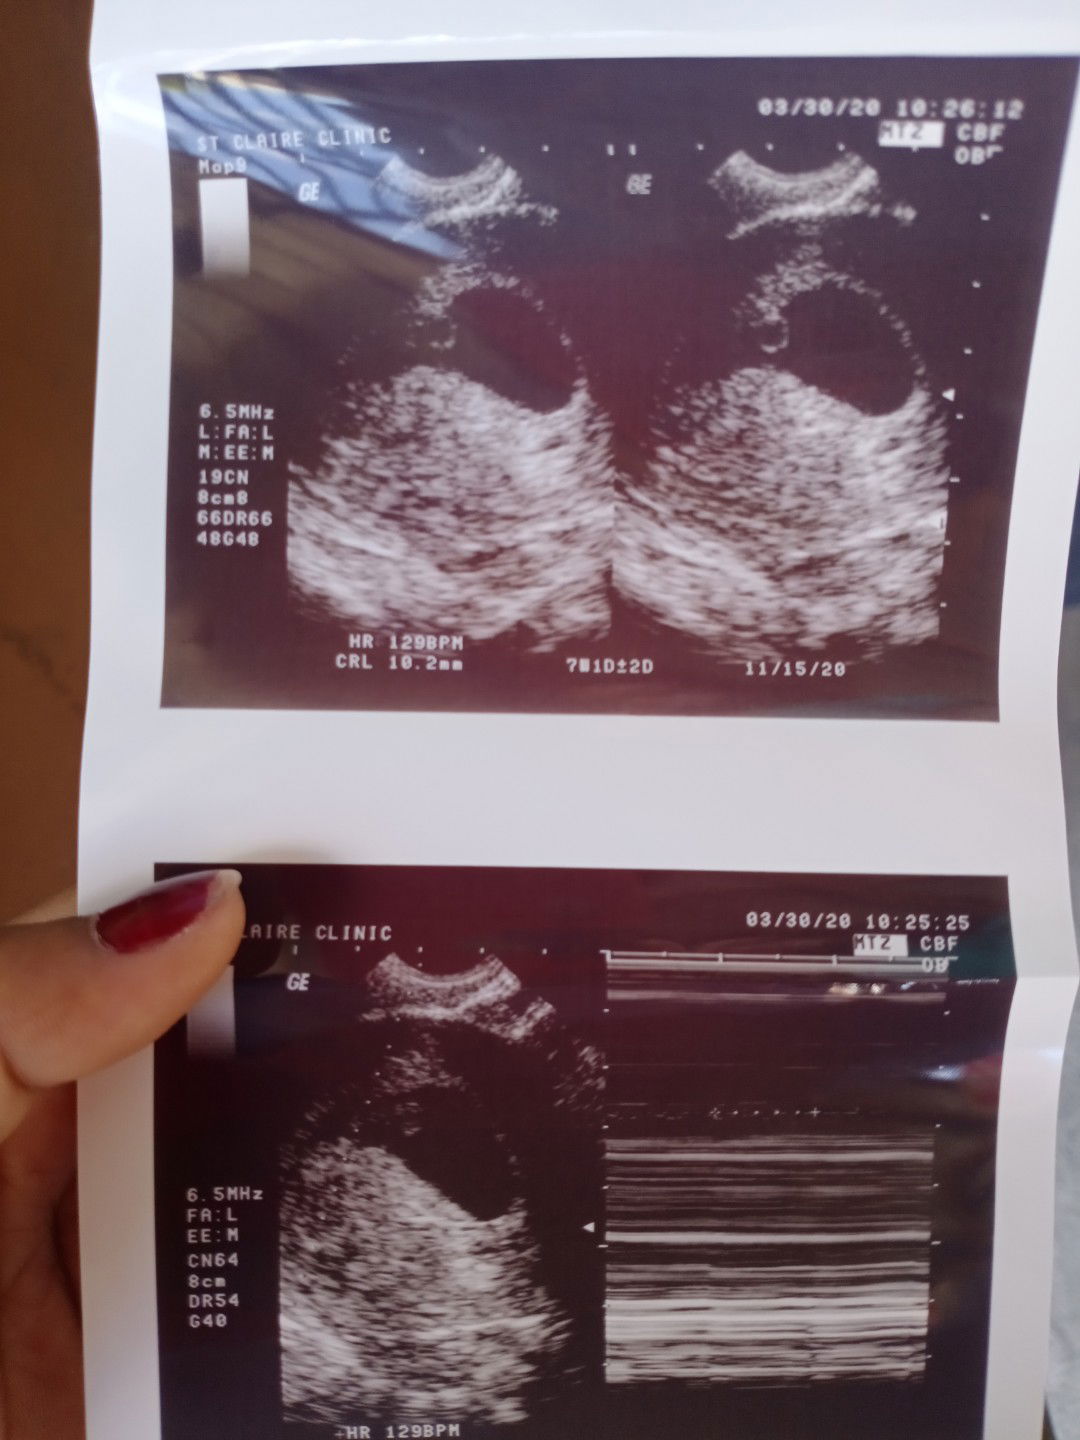

Nagspotting ako wednesday brown discharge gabi un. Kinabukasan nagpacheck up ako. Una bngyan ako pangpakapit bngyan dn ako request para mkpag paultrasound sa ibang lying in. Kc monday pa ultrasound nila. So nagpaultrasound ako. Wala daw heartbeat. Hindi daw buhay ung baby. Then balik ako sa pinagpacheck upan ko. Hnd n nila pinaliwanag sakin kung bakit ako nakunan kung bakit walang heartbeat. Pinaderetso na nila ko ng ospital need ko na daw ng OB. Nagspotting lng nman ako ng konti brown lng sya na prang tubig kc wala syang amoy. D sya amoy malansa. Pumunta naman ako ngyon ng ospital pra malaman kung raraspahin ako kase hnd ako dinudugo kung nakunan man ako. Pinag laboratory test nila ko. Normal lhat ng result. Sbi nalang hintayin ko nlng daw kusang lumabas yung dugo tska ako Bumalik kapag lumbas na at may ksmang buo. Para malaman kung raraspahin ako. Thursday non ng gabi pag uwi ko my spotting ulit at red na sya. Dugo na tlga kaya lng konti pa din. Kala ko magtutuloy na. Pero hanggang ngyon wala na hnd na nasundan. Any advice naman hnd ko kse alam kung mali lng ung nagultrasound sken.